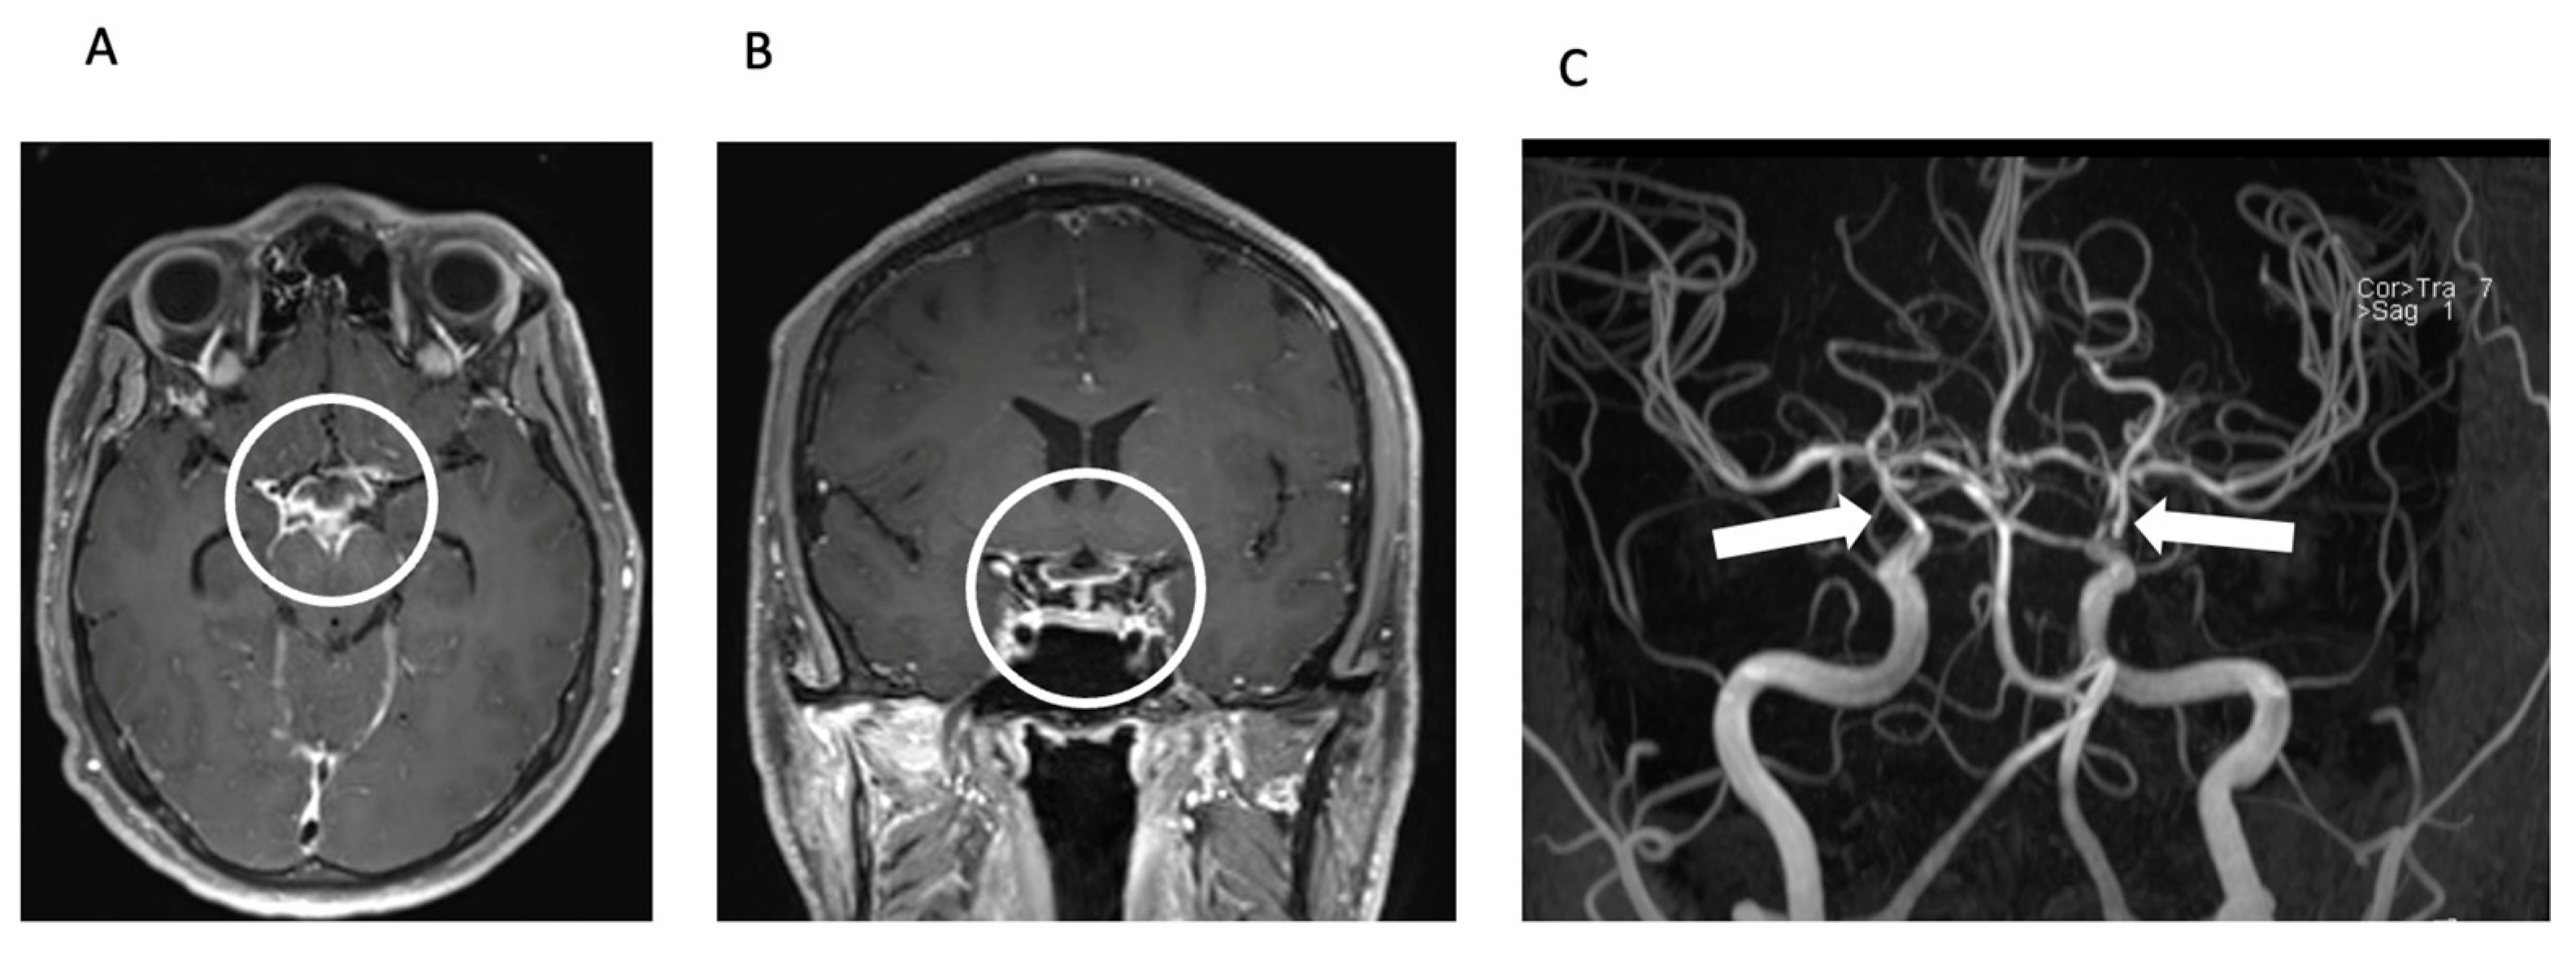

The radiologist’s observation of intraventricular contrast agent enhancement led to a suspicion of pyogenic meningitis with concomitant vasculitis (Figure 2).

Meningitis and secondary CNS vasculitis on MRI. Axial (A) and coronal (B) reconstructions of contrast-enhanced T1 SPACE image showing basal contrast enhancement predominantly in the basal cisterns around the circulus of Willis (circle). TOF MR angiography (MIP, posteroanterior view—(C)) shows severe stenoses of the intradural proximal cerebral arteries, predominantly in the distal ICA including carotid T bilaterally (arrows).